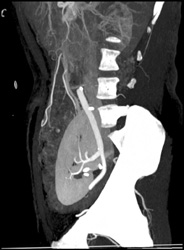

Transitional Cell Cancer (TCC) of Left Kidney